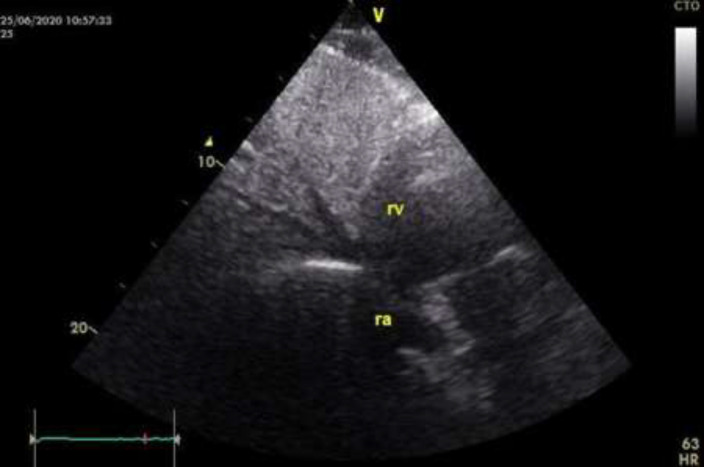

Case presentation: A 23-year-old male with no cardiovascular risk factors or prior cardiovascular disease presented with atrioventricular reentrant tachycardia that converted to sinus rhythm after adenosine administration. The patient was scheduled for an electrophysiology study with catheter ablation if indicated. During the procedure, catheter advancement into the right atrium was unsuccessful, raising suspicion of an interrupted inferior vena cava (IVC). Radiofrequency ablation was subsequently performed successfully via the subclavian vein approach. Post-procedural computed tomography (CT) imaging confirmed interruption of the IVC.